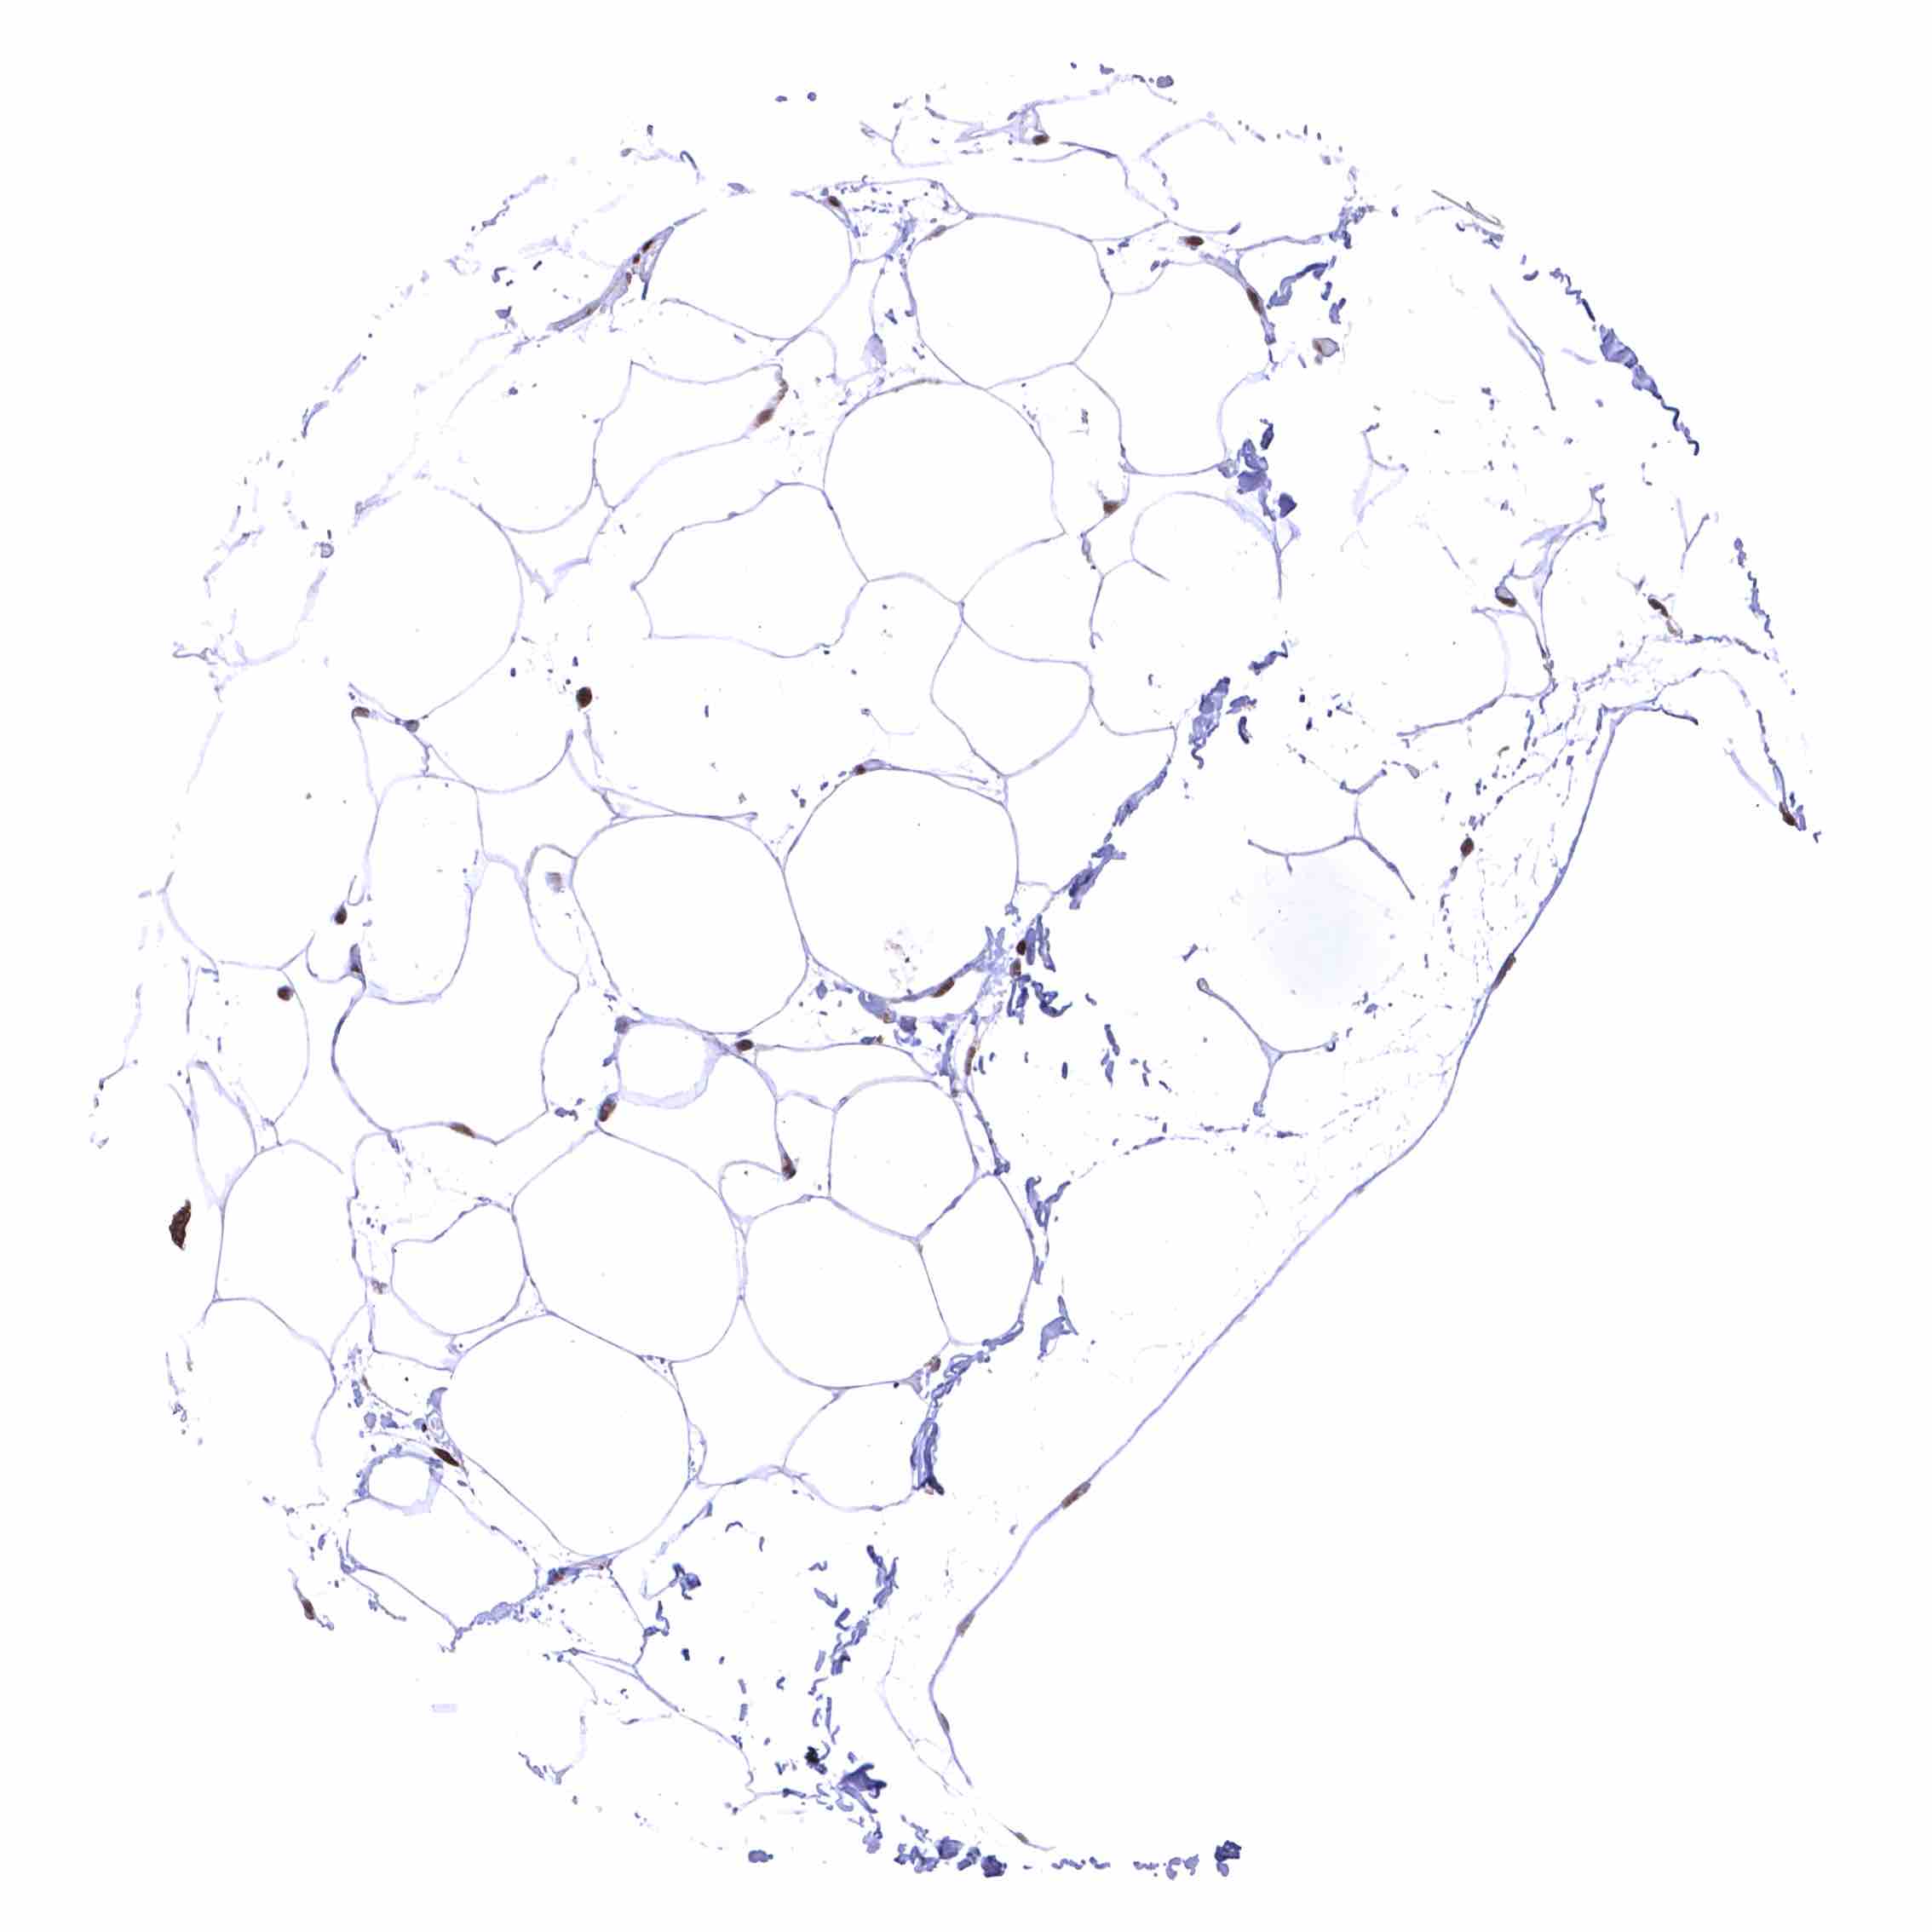

Fat – Distinct nuclear BRD4 staining of fat cells.